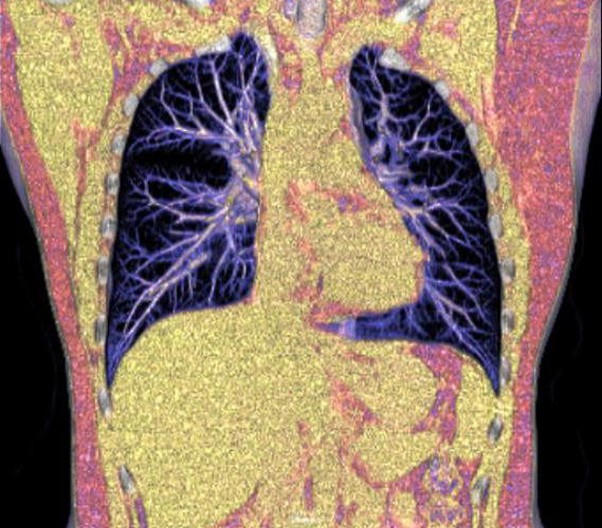

The 1024-pixel image matrix brings superior image clarity (0.6 mm slice thickness) and stimulates the early detection of small lesions, thus improving diagnostic reliance.

ScintCare CT 16 incorporates an entirely digital integrated ScintiStar detector, which was solely developed by MinFound, from material to the whole structure design, based on the technical know-how of our skilled scientific team. The system produces high-resolution images with a low radiation dose and an excellent signal-to-noise ratio.